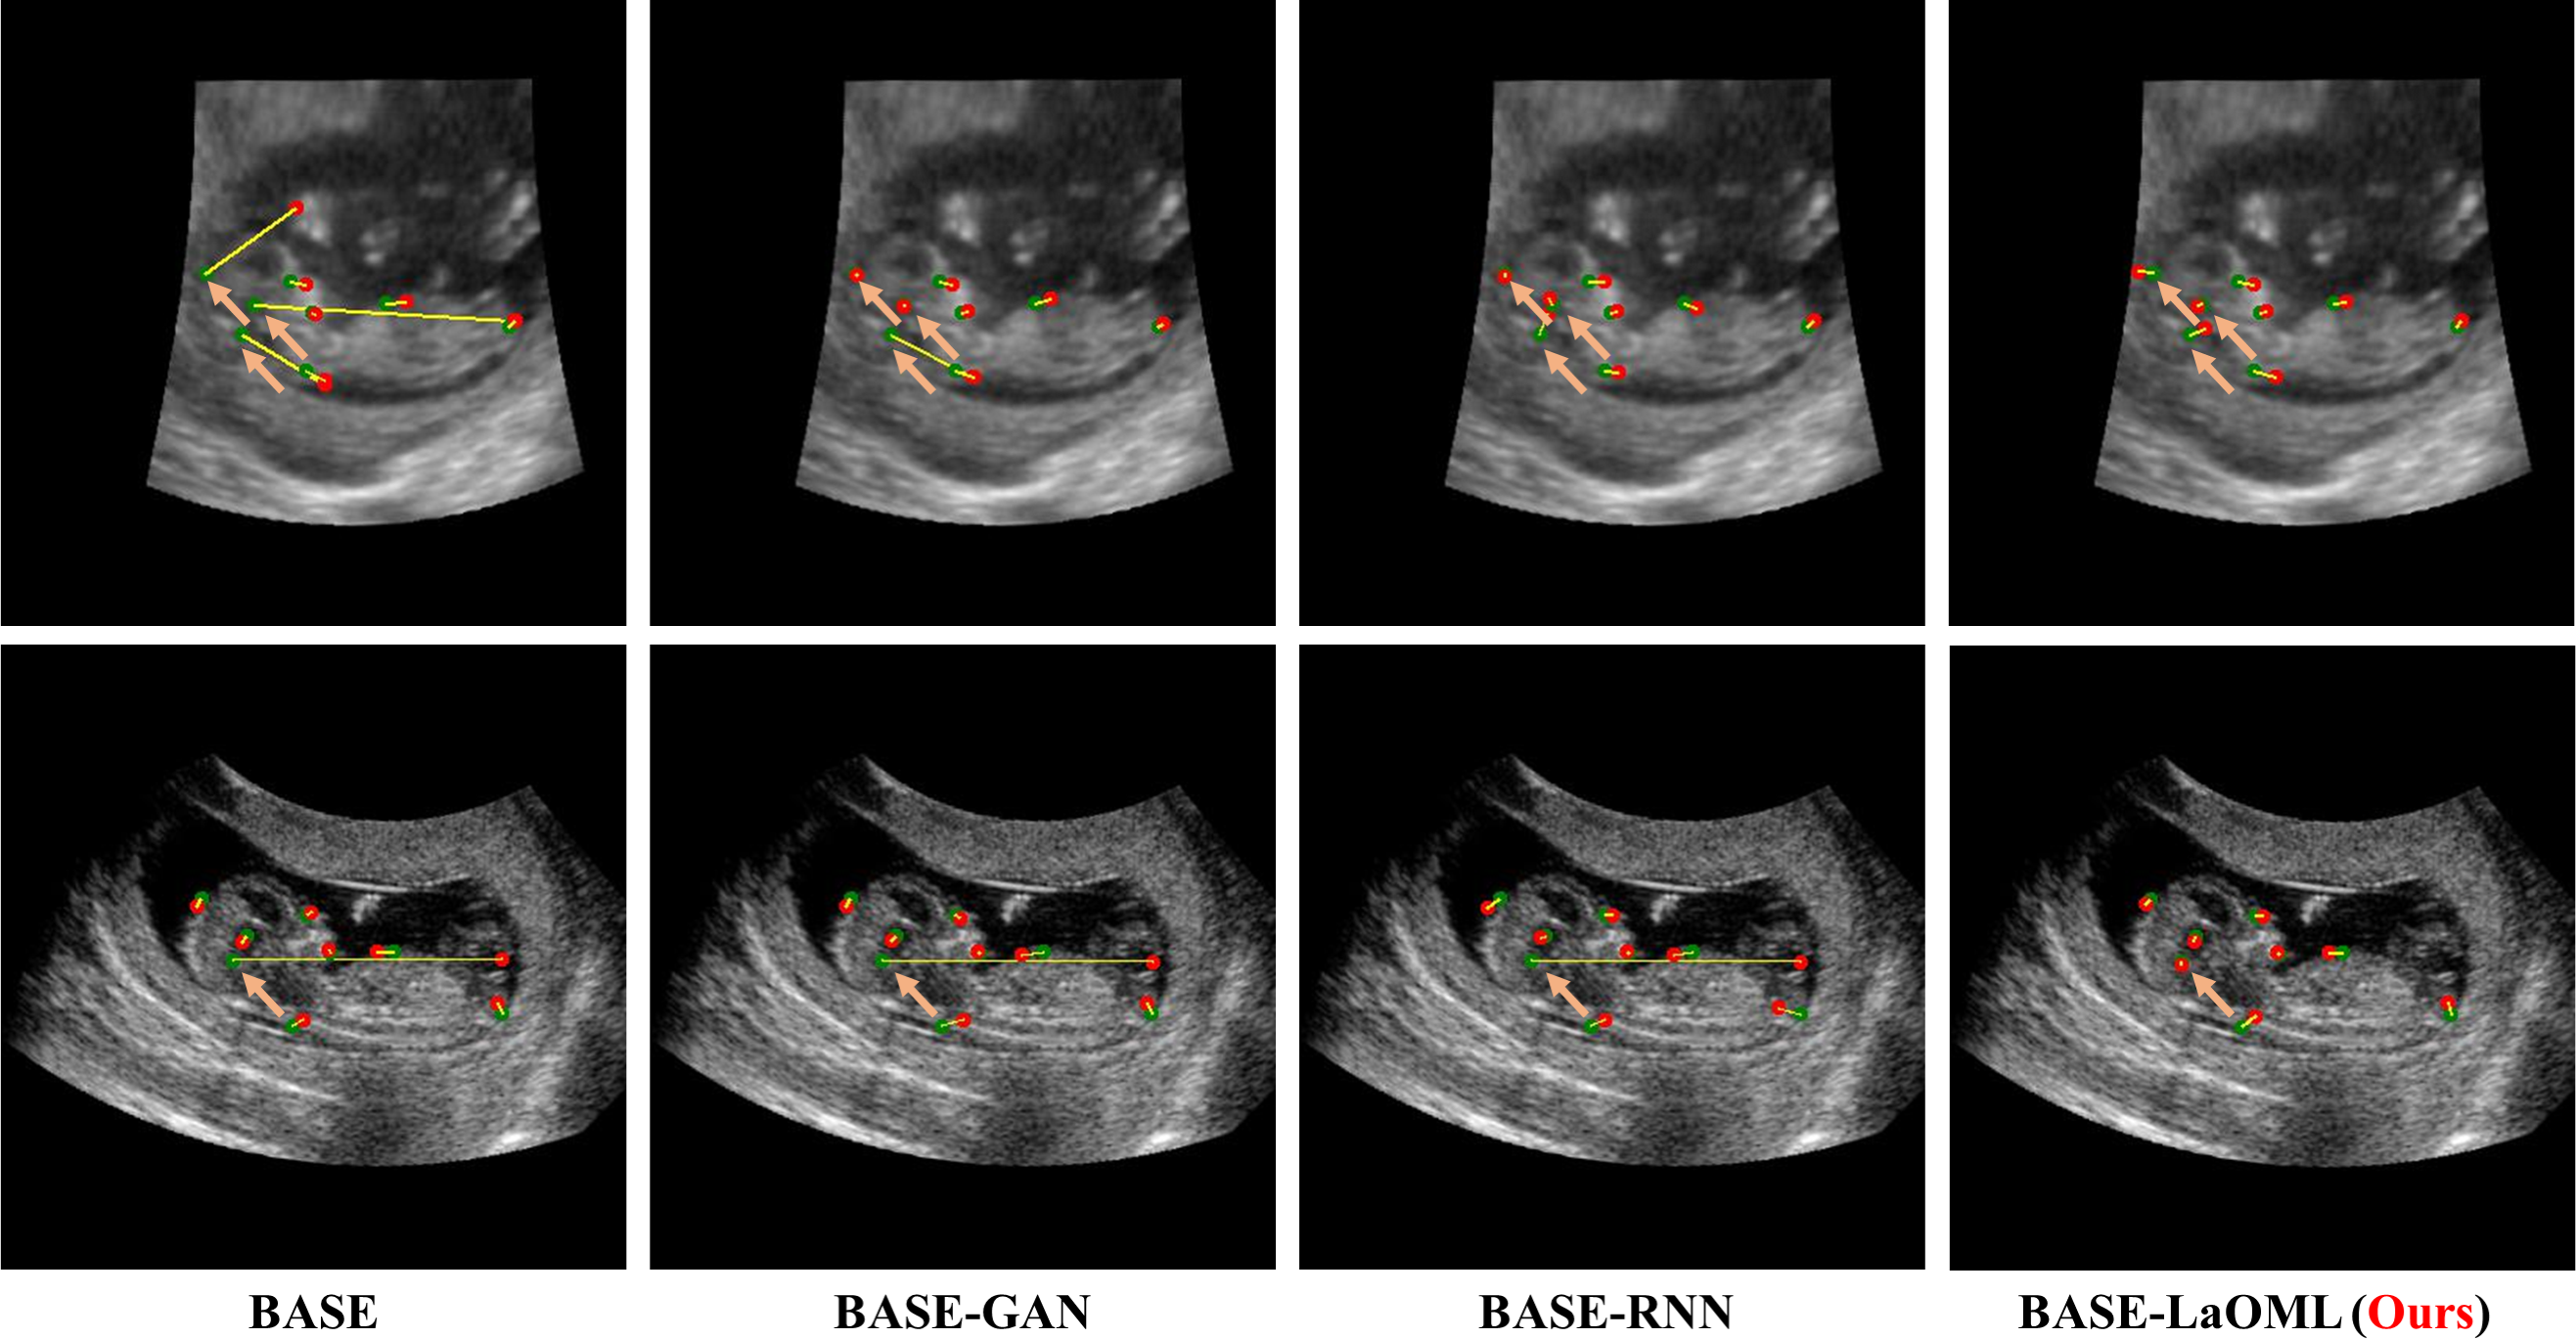

Table 1 presents the landmark detection results when different strategies are employed on the BASE network. Our proposed BASE-LaOML significantly outperforms BASE, BASE-GAN, BASE-RNN, and BASE-C, achieving a good improvement in mean MRE of all landmarks. The LaOML attains the lowest MRE average and STD and achieves the greatest improvements of MRE on 6 of 8 landmarks, while GAN and RNN only enhance the baseline to a certain extent. Moreover, the direct usage of the exact pixel’s coordinate deteriorates the localization accuracy compared to the heatmap regression methods. Fig. 4 shows the curve between PCK and the threshold ranging from 2 to 8 mm for the heatmap regression methods. The BASE-LaOML also tops the task and achieves the highest PCK result, outperforming BASE by 2 under almost all the thresholds. Both BASE-GAN and BASE-RNN also show some improvements in PCK. Nevertheless, the BASE-LaOML still outperforms these two methods in both MRE and PCK (Table 1 and Fig. 4). We also visualize some examples of the localized landmarks for the prenatal ultrasound (Fig. 5). The results suggest that using LaOML restrains the extreme errors of landmarks’ localization. However, GAN or RNN cannot suppress these errors effectively, though they can alleviate this problem. Moreover, Fig. 6 presents the process of optimizing using our proposed LaOML method, implying the inherited uncertainty and inconsistency in landmark heatmap. These qualitative and quantitative results suggest that our proposed method is comparatively more robust to speckle noise and achieves proper localization in ultrasound images.

We show the results of comparing our BASE-LaOML to BASE-RNN, BASE-GAN, BASE-C, and other state-of-the-art methods on the Test2 subset of the ACXRLDC dataset in Table 2. We offer the PCK under 2 mm, 2.5 mm, 3 mm, and 4 mm threshold and the Mean (S.D.) MRE. Our baseline model obtains only a little worse result than most state-of-the-art methods, although it does not make additional network constraints. As illustrated in Fig. 7, landmarks in Cephalometric X-Ray images prefer the different to generate the heatmap ground truth. We conjecture that choosing an appropriate instead of a commonly small can improve the model. We validate this assumption in the following ablation studies by using different . Compared to the BASE, the BASE-LaOML method performs preferably in landmark localization with MRE improvement of 0.18 mm in average and 2 mm in standard deviation. When comparing with other state-of-the-art algorithms, it is clear that the average MRE for most of the other results is above 1.45mm. Also, in line with the prenatal ultrasound dataset results, the Base-C method has the worst localization performance among all the compared methods. Fig. 8 presents some examples from different patients of the ACXRLDC dataset. Most predicted landmarks correspond to the positions where they are supposed to be. Also, the results support that the proposed LaOML alleviates the extreme errors in landmarks’ localization.